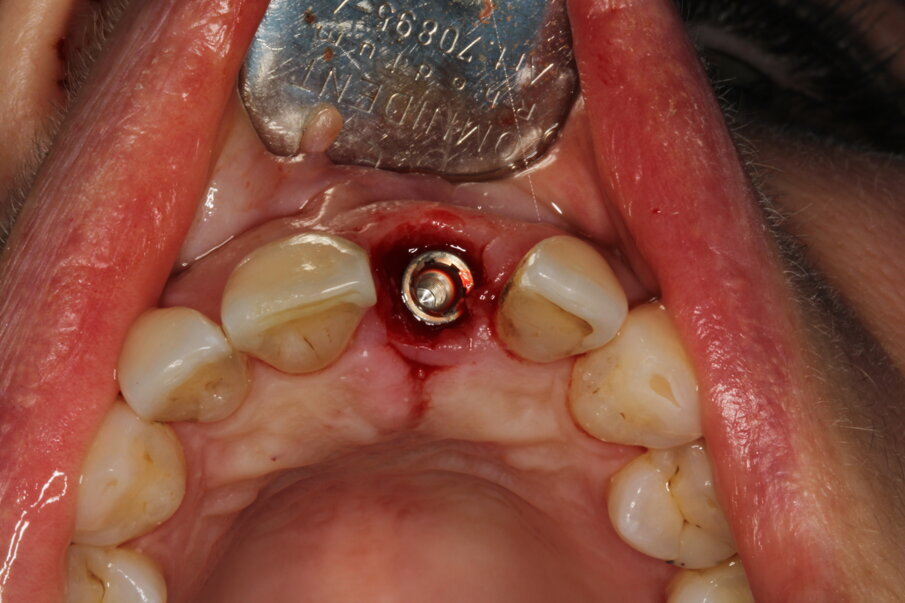

Local anaesthesia was performed with 2% mepivacaine with 1:100,000 adrenaline. Preventative antibiotic therapy with amoxicillin (1 g, b.d. for five days) was prescribed, aided by use of a 0.2 % chlorhexidine mouthrinse three times a day for one minute. The tooth was extracted and the sulcular epithelium removed with diamond burs. The milled surgical template (Figs. 12 & 13) served as a guide for the first 2 mm diameter pilot drill (Fig. 14). Thus, the planned depth, position and angulation of the osteotomy were obtained. The drill sequence was completed freehand, using tapered 3.0 and 3.4 mm drills. A Neoss Pro- Active Tapered Implant of 4 mm in diameter and 13 mm in length was inserted flush with the mesial/palatal/distal bone, motor driven up to a torque of 50 Ncm and then with a manual wrench (Fig. 15). The correct position of the internal hex was verified by checking the references on the implant driver, which ideally points in the buccal direction. Resonance frequency analysis with Penguin RFA (Integration Diagnostics Sweden) determined an ISQ value of 73/76. At this stage, a Neoss Esthetic Healing Abutment with a ScanPeg was connected to the implant (Fig. 16). A flap was then raised after a vertical incision of the frenulum and the expected buccal exposure of the implant neck was evident. Autogenous bone harvested from the drills was positioned directly on the implant surface (Fig. 17), followed by a bone substitute on top of it and on the buccal cortical bone (Fig. 18). This material was covered with a resorbable membrane (Fig. 19). The mobilised flap was then repositioned by rotating it coronally and fixed with single sutures (Fig. 20). The removable partial denture was adapted and delivered (Fig. 21). An immediate postoperative CBCT scan of 60 x 60 mm was performed, and it confirmed a perfectly centred implant position (Figs. 22 & 23).